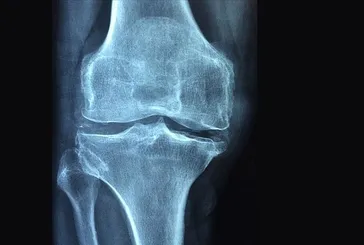

Hareket et osteoporozu geç

Hareket et osteoporozu geç Osteoporoz yani kemik erimesi, daha çok kadınlarda görülüyor. Özellikle menopozdan sonra artış gösteriyor. Doç. Dr. Ahmet İnanır, “Hareketsizlik tetikliyor. Düzenli spor yapın” diyor.

Kemik erimesi yaşa bakmaz!

Kemik erimesi yaşa bakmaz! Kemik erimesi, hayat kalitesini düşürüyor. Doç. Dr. Hakan Sofu, genellikle yaşlılarda meydana gelen hastalığın gençlerde de görüldüğünü söylüyor.

Kemik erimesi ailenizin eseri

Kemik erimesi ailenizin eseri Sırt ağrısı ve kırıklara yol açan kemik erimesi, yaşam kalitesini düşürüyor. Daha çok kadınları tehdit ediyor. Uzmanlar uyarıyor: Ailesinde bu hastalık olanlar kontrolleri aksatmasın.